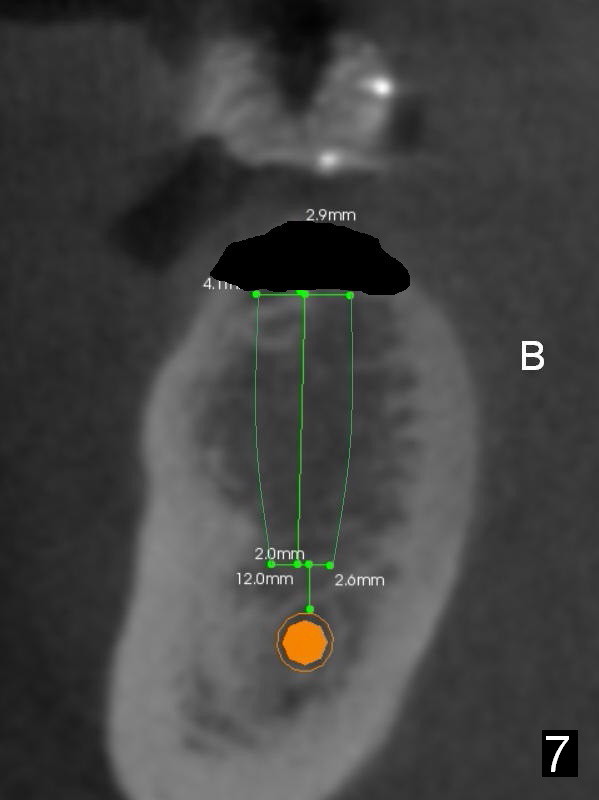

The first implant will be placed at #29 (Fig.4,5). The pointed ridge will be flattened to start osteotomy (Fig.6,7 (surgical handpiece)). The buccolingual dimension of the flattened ridge should be ~ 6 mm. The initial depth will be 12 mm. Take the 1st PA. A restorative high speed handpiece may be needed to remove the enamel of the mesial surface of #30 and the distal surface of #28 to increase space for implant placement.